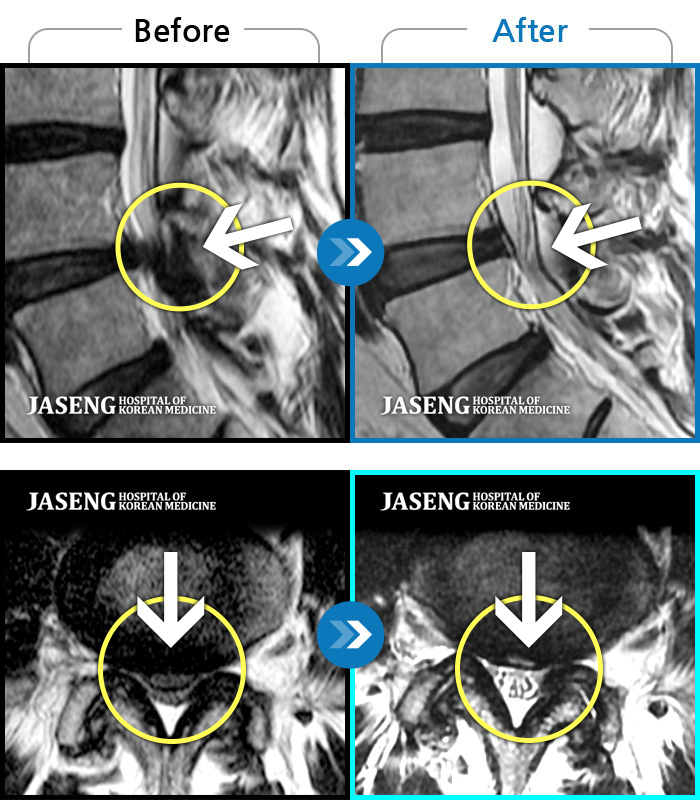

MRI로 보는 치료결과

1,169건의 MRI 전후 사진으로

터진 디스크 흡수 사례를 확인하세요.

[촬영시기:23.02.03~24.02.14]

[촬영시기:23.02.03~24.02.14]

[수원_허리디스크] 허리 통증과 좌측 대퇴부 저림과 당김조회수 0 2024.11.21 -